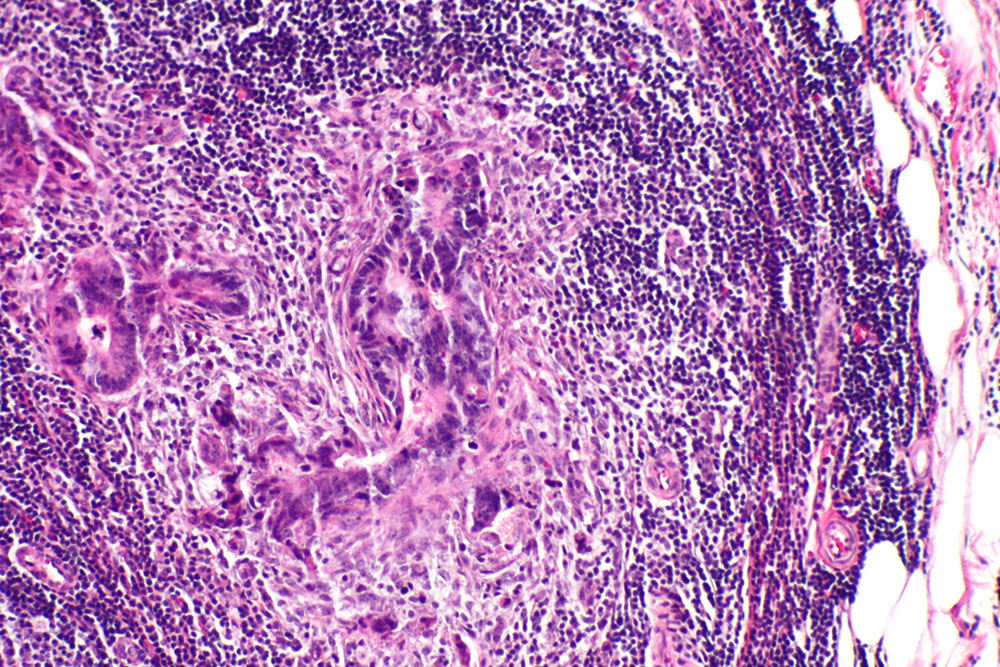

VRSTE MALIGNIH TUMORA PREMA PORIJEKLU STANICA

Rak se može razviti u bilo kojem dijelu tijela, te se prema vrsti stanica odnosno prema postanku dijeli na:

• karcinome - zloćudne novotvorine porijeklom iz epitelnih stanica;

• sarkome - zloćudne novotvorine porijeklom iz mezenhima ili njegovih derivata (mezenhim je prvobitno vezivno tkivo koje se javlja još u embrionalnom stadiju)

• limfome i mijelome - zloćudne novotvorine porijeklom iz retikuloendotelnog i limfatičnog sustava.

Rak se, s obzirom u kom dijelu tijela se razvio, može manifestirati na različite načine. Za konačnu dijagnozu najčešće je potrebna mikroskopska analiza tkiva dobivenog biopsijom. Kada se jednom dijagnosticira, terapija se najčešće sastoji od kirurške operacije, kemoterapije i zračenja.

Stupanj malignosti tumora je pojam koji se koristi najviše u patologiji i odnosi se na nekoliko osnovnih karakteristika malignog tkiva i stanica i broj stanica koje su trenutno u diobi. Indirektno ovaj parametar govori o agresivnosti tumora, ali i o njegovoj osjetljivosti na citostatike i ionizirajuće zračenje jer su stanice koje se dijele osjetljivije na ove agense.